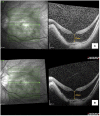

Case presentation: An elderly female patient with bilateral high myopia and pre-existing myopic foveoschisis underwent uncomplicated sequential cataract surgeries 2 weeks apart. She was able to achieve a satisfactory visual outcome for her left eye with stable myopic foveoschisis and visual acuity of 6/7.5, near vision N6. However, her right eye vision remained poor postoperatively, with a visual acuity of 6/60. Macular optical coherence tomography (OCT) revealed a new right eye outer lamellar macular hole (OLMH) and outer retinal detachment (ORD) within pre-existing myopic foveoschisis. Her vision remained poor after 3 weeks of conservative management, and she was offered vitreoretinal surgical intervention with pars plana vitrectomy, internal limiting membrane peeling, and gas tamponade. However, she refused surgical intervention, and her right vision remained stable at 6/60 over 3 months of follow-up.